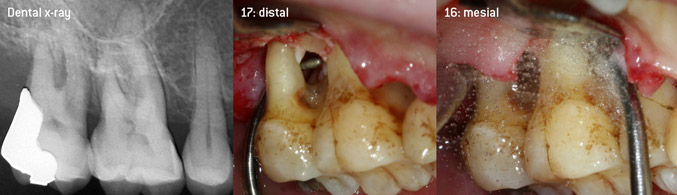

As initiators of the development of the new diamond-coated 3AP air scaler tip, the two dentists recognized the need for improvement of the handling restrictions of the commercially available diamond-coated tips, especially during furcation treatment and when working in tight intraosseous pockets. This should be possible for both non-surgical (Figure 2) and surgical (Figure 3) procedures.

Open debridement of the furcations on teeth 16 and 17

Fig. 3: Open debridement of the furcations on teeth 16 and 17 in case of advanced attachment loss

The aim was to develop a universally applicable tip in order to avoid time-consuming tip changes. In addition, it should be easier to use the new working tips in tight intraosseous pockets from distal and at the distal furcation entrance of maxillary molars, allowing more effective use of instruments as a result. This was achieved by employing an instrument curve with a larger diameter (Figure 1), which is highly advantageous for closed debridement on teeth with advanced attachment loss and involvement of furcation in particular (Figure 4).